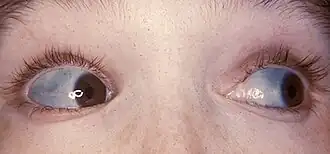

Sclérotiques bleutées

La sclérotique est l'enveloppe blanche et opaque de l’œil. Elle est constituée d'un tissu fibreux solide qui entoure le globe oculaire. Elle contient des vaisseaux sanguins fins. Lorsque l'œil est irrité, les vaisseaux sanguins vont se dilater : c’est ce qui est responsable de la couleur rosée ou rouge de l’œil. Les patients atteints de la maladie des os de verre présentent des sclérotiques bleutées.